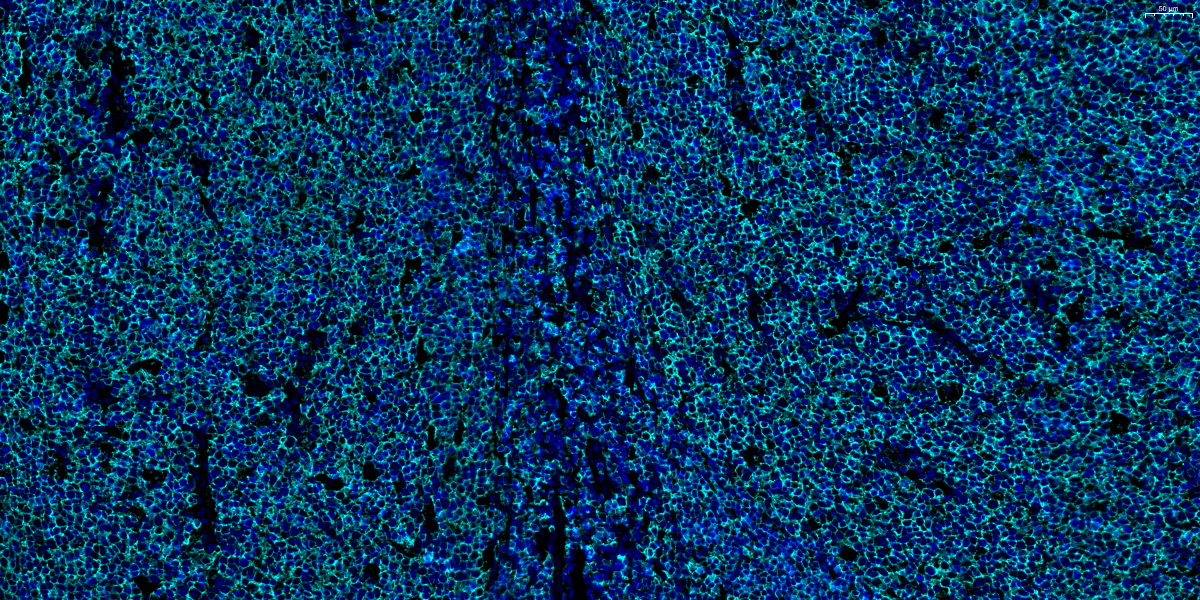

480-CD20-扁桃体-20X